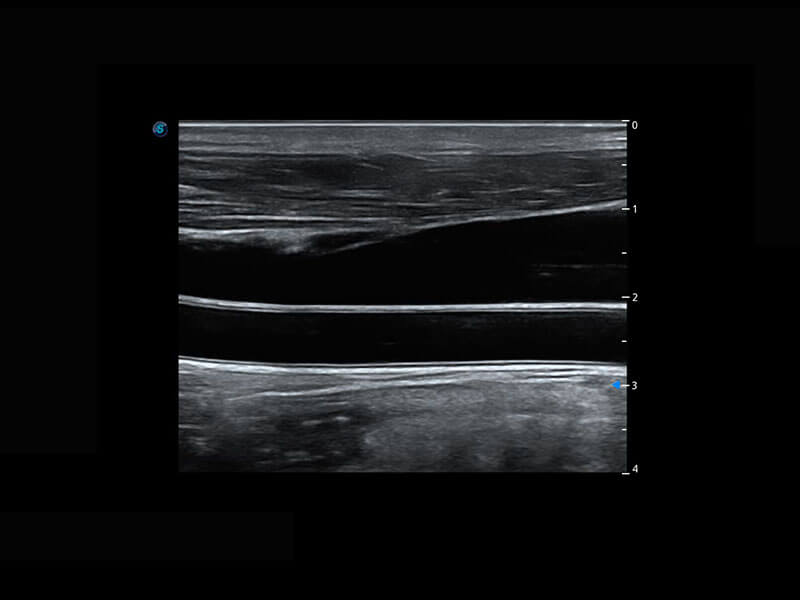

乳腺超声 / 新生儿

P60搭载宽频带线阵探头、宽景成像、弹性成像技术,为您提供乳腺应用方案。P60支持高频相控阵探头、线阵探头、腹部高频探头、腹部微凸探头等,丰富的探头群搭载敏感的彩色血流成像,适用于新生儿多种脏器检测要求,满足新生儿筛查需求。

• 乳腺导管癌

• 新生儿脊髓圆锥